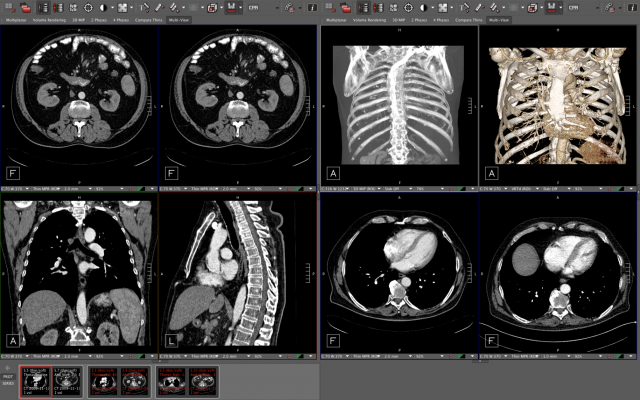

November 18, 2019 — Visage Imaging, Inc. (Visage), a wholly owned subsidiary of Pro Medicus Ltd. (ASX: PME), has announced Visage will be exhibiting under the theme of "Platform for the Future—Powered by Speed," highlighted by the demonstration of the Visage 7 Enterprise Imaging Platform, at the Radiological Society of North America (RSNA) 2019 annual meeting (Visage Booth 7524, McCormick Place-North Hall), Dec. 1-5, in Chicago, Ill.

Visage 7 has advanced Enterprise Imaging based on the proven ability to replace legacy PACS for imaging organizations of all sizes and local, regional or national scale. Five of the 2019-2020 top 20 ranked U.S. hospitals have chosen Visage 7, more than any other PACS.

One of the key drivers of this change has been the relentless growth of datasets produced by modern imaging modalities such as large cross-sectional (CT/MR) and digital breast tomosynthesis (DBT), and now high-resolution DBT ("High-res DBT"). These datasets, which are often combined with numerous prior imaging studies, are creating major bottlenecks for legacy 'compress and send' technology.

- High-res DBT. Visage 7 supports the diagnostic interpretation of high-res DBT, delivered on-demand and in real-time, by ultrafast server-side processing.